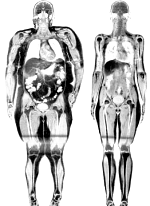

The fatter you are, the more likely it is that you don't have a sunny view of life. Studies show that obesity increases the chance of having symptoms of depression. You'd expect that overweight people who lose weight would become more cheerful as a result. And this is indeed the case researchers at the University of Pennsylvania discovered when they did a meta-study. As long as pharmacological slimming aids are not involved.

In the figure above you can see the effect of a weight loss approached based purely on medicines such as orlistat, sibutramine or rimonabant, compared with the effect of a placebo. As you can see, symptoms of depression were not reduced by this approach.